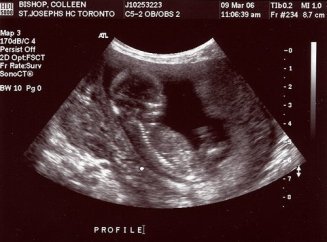

Tak wygląda płód w 11 tygodniu (klikalny):

USG w 11 tygodniu pokaże wyraźnie zarysy małego człowieka. Na wysokiej klasy sprzęcie ze szczególnie dobrą lokalizacją dziecka możesz już określić jego płeć. Jednak dane mogą być niedokładne.

Zdjęcie USG: